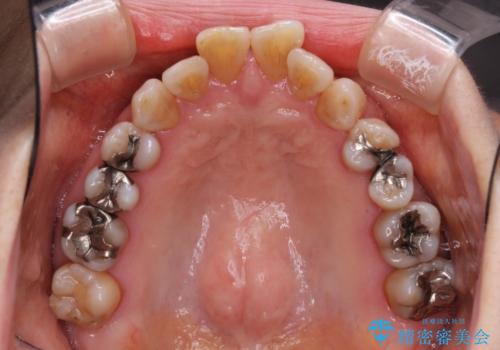

- 突出した口元を引っ込めることを希望して来院された患者様です。

上下左右第一小臼歯4本を抜歯して、口元を改善するワイヤー矯正を行うこととしました。